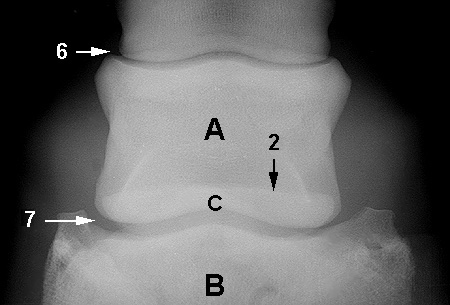

Radiograph of the Dorsopalmar(plantar) view

Dorsopalmar(plantar) view